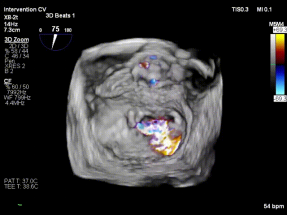

红区脱垂(DMR):复杂解剖下的精准修复

【图片1:术前超声图】

病例1为典型退行性二尖瓣脱垂(DMR),术前超声提示外交界瓣叶明显脱垂,反流程度达重度(4+),伴随活动后气促等心衰症状。由于病变位于“红区”,瓣叶结构复杂、对合不稳定,属于TEER治疗中的高难度类型。